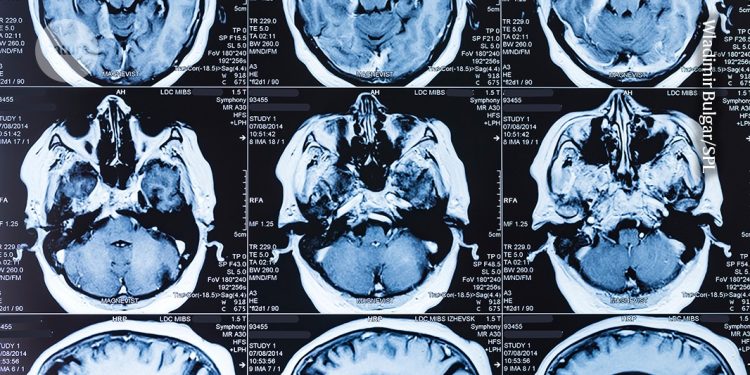

La resonancia magnética se encuentra entre las tecnologías innovadoras que surgieron de la ciencia fundamental impulsada por la curiosidad.Crédito: Wladimir Bulgar/SPL

La reacción en cadena de la polimerasa, la ciencia fundamental detrás de las pruebas de PCR utilizadas para identificar bacterias y virus que se convirtieron en parte de la vida diaria durante la pandemia de COVID-19, se originó a partir del trabajo con bacterias encontradas en aguas termales por los microbiólogos Hudson Freeze y Thomas Brock de la Universidad de Indiana en Bloomington. La resonancia magnética (MRI) surgió del estudio de la Propiedades físicas fundamentales del núcleo atómico.y los estudios de lagartos venenosos desempeñaron un papel clave en el desarrollo de fármacos como Ozempic que imitan la hormona GLP-1. Los televisores de pantalla plana tienen su origen en estudios sobre sustancias químicas aisladas de las zanahorias. La sección de noticias cubre siete ejemplos destacados, pero hay muchos otros.